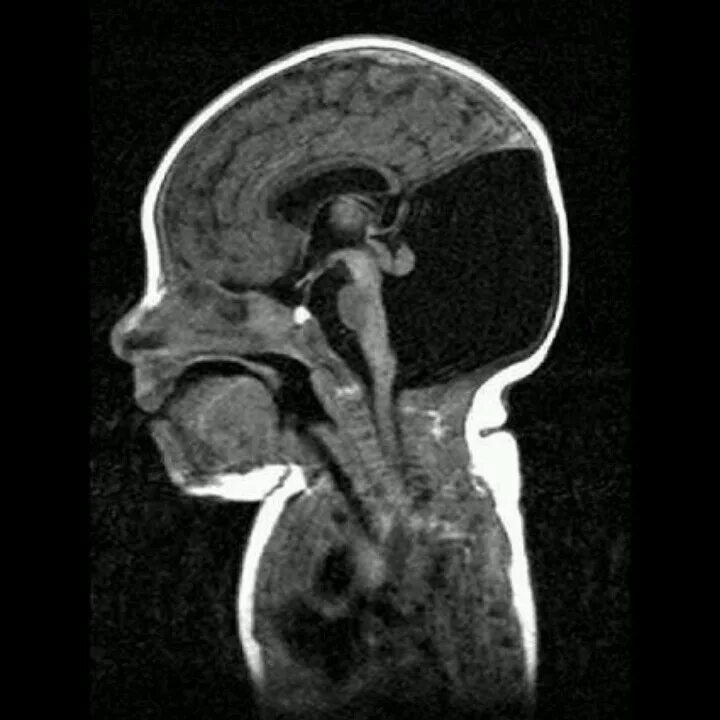

Денди уокер у взрослых